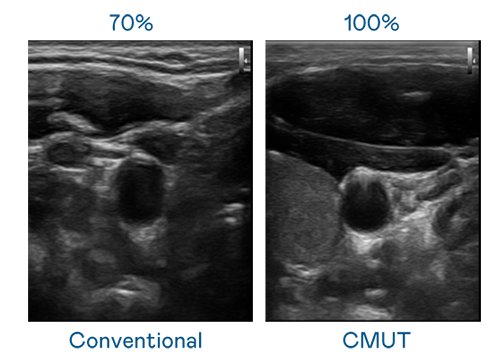

CMUT 技术是一种用电容式微机电元件来产生超音波讯号的技术。与传统 PZT 压电式技术相比,CMUT 频宽增加 30%,更宽频的超音波讯号让影像解析度大幅提升,是实现高影像品质医疗超音波扫描、促进精准医疗发展的关键技术。

大频宽带来超清晰影像

超音波影像的解析度高低,首先取决于探头能发出的讯号频宽。Z6·尊龙时凯 CMUT 可提供高清晰的超音波讯号,提供高频宽、高灵敏度、影像纹理细节更高的超音波影像,协助医护人员缩短影像判读时间及利用精准的医疗影像进行诊断。